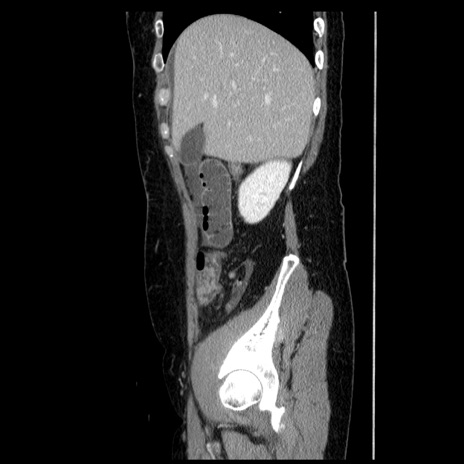

冠状断像